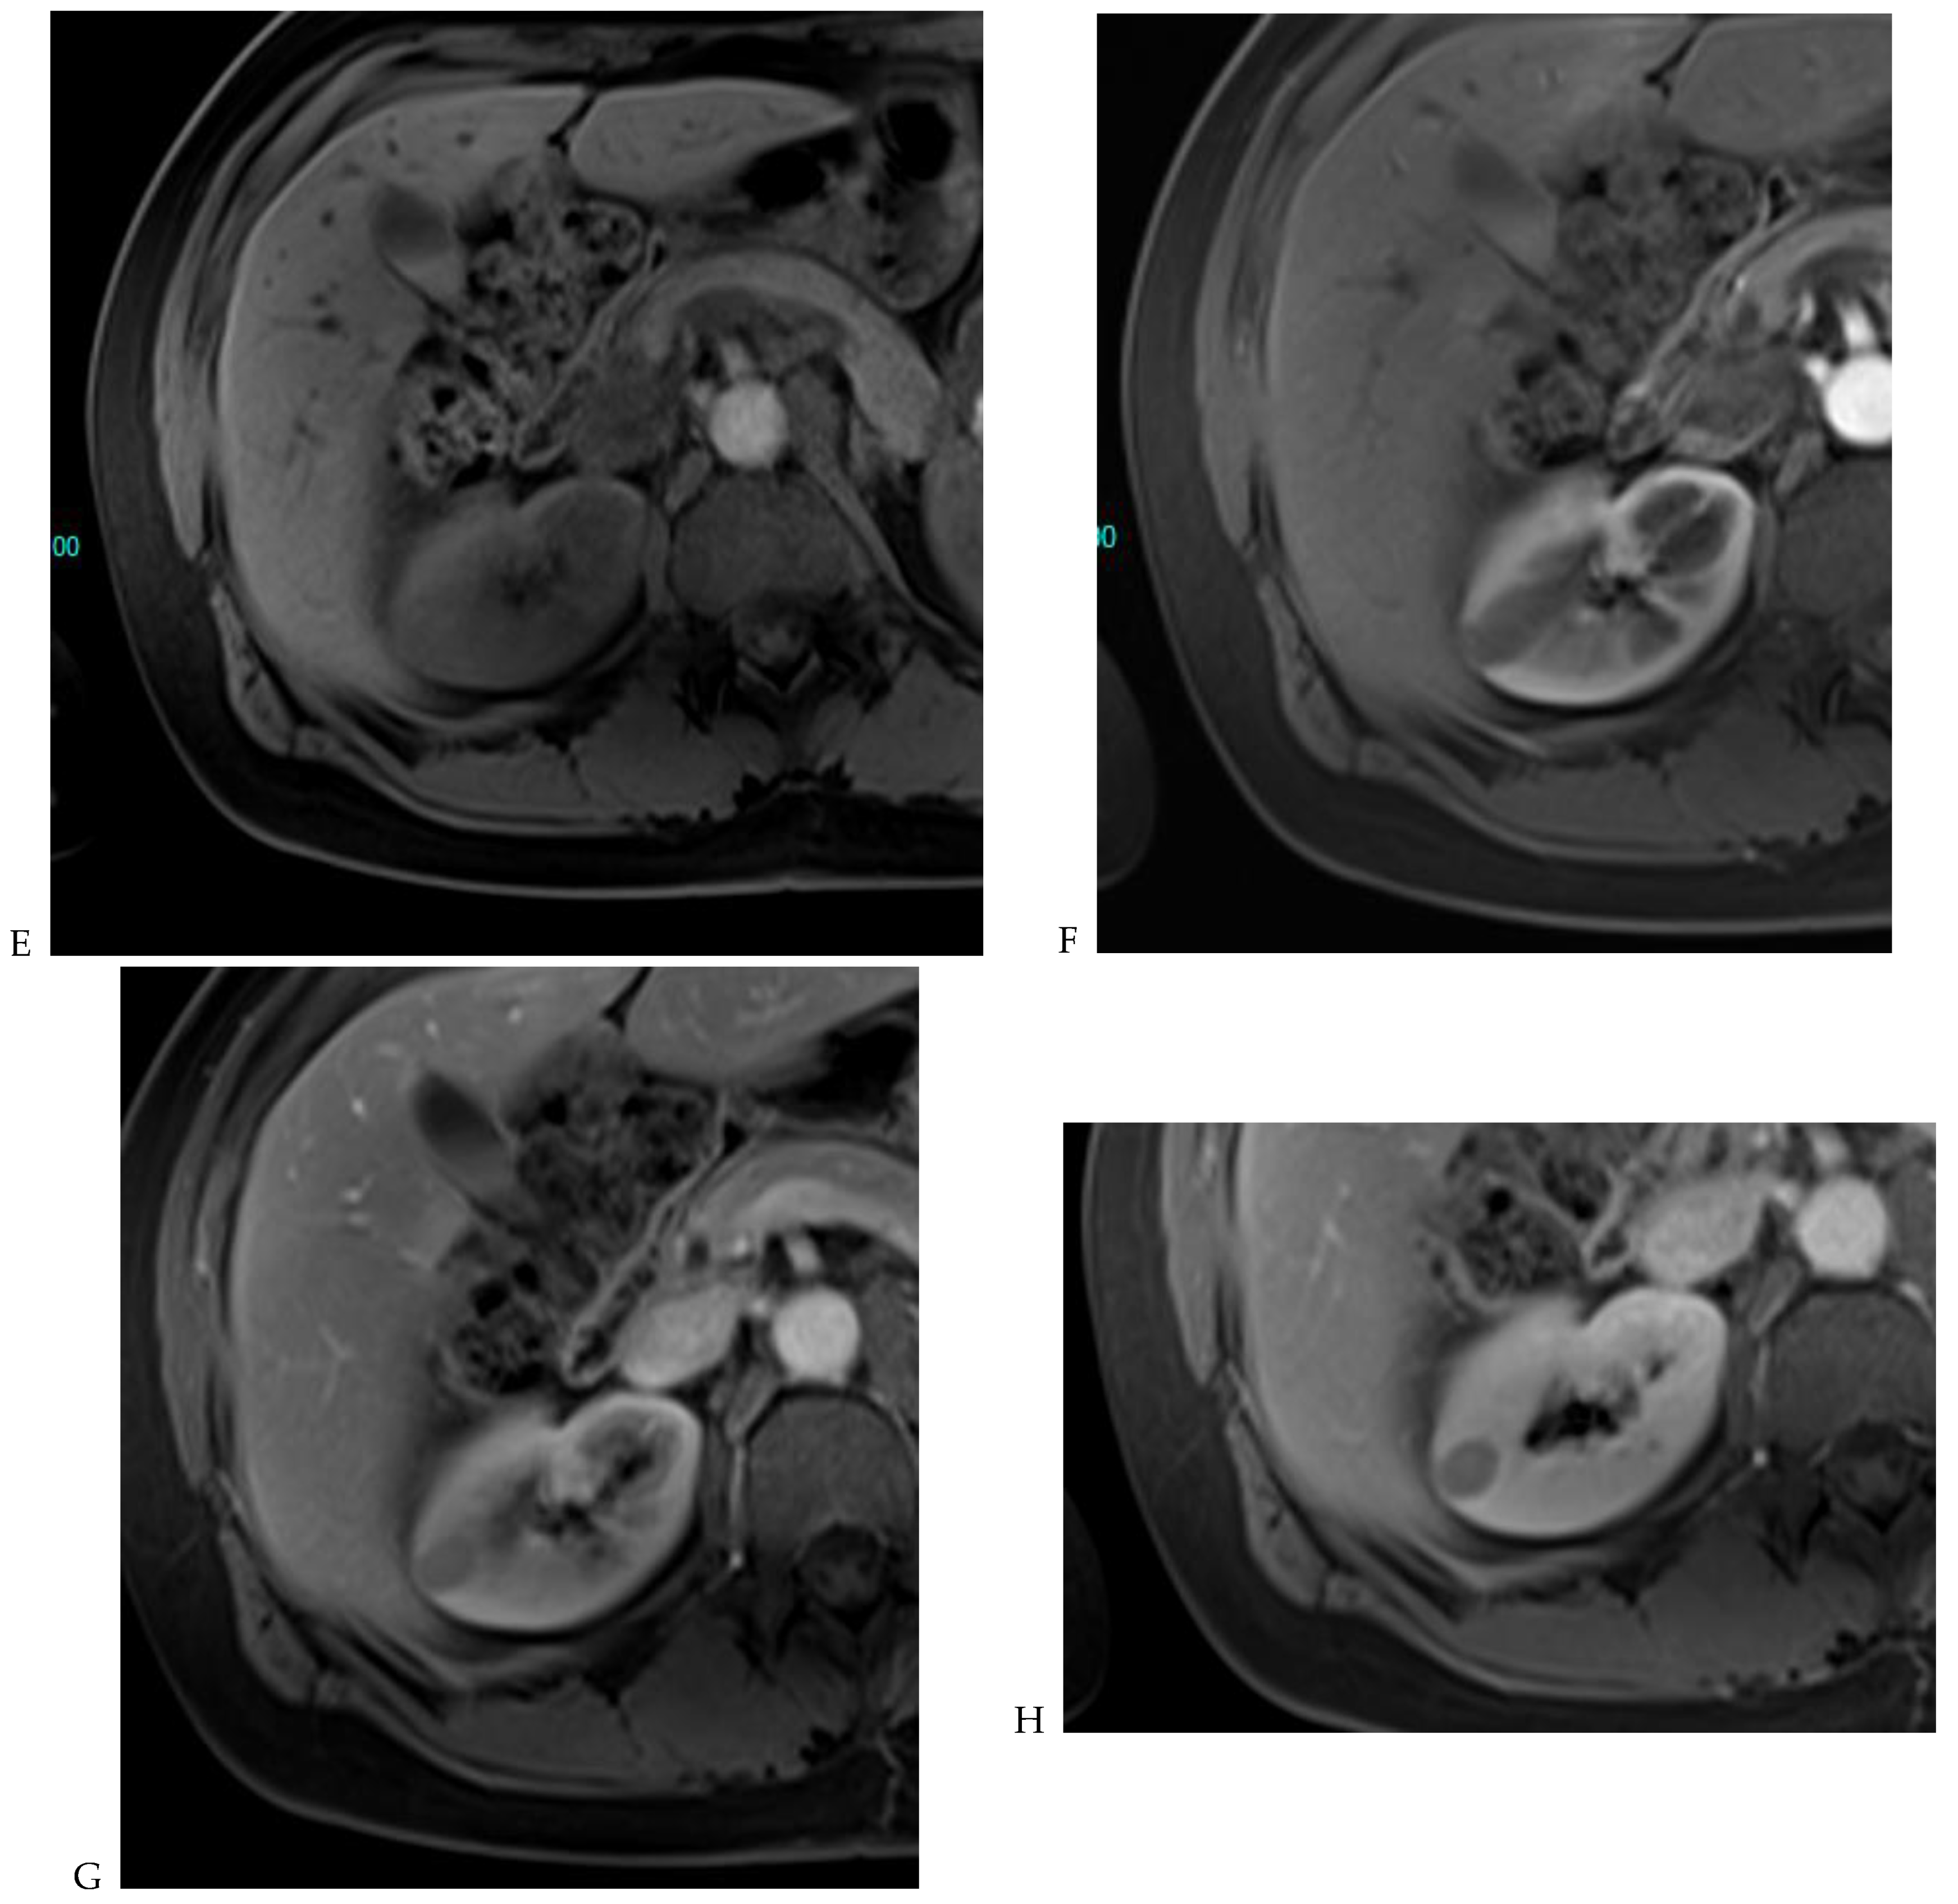

Figure 8.

Same lesion as Figure 3. Chromophobe renal cell carcinoma in the left kidney of a 68-year-old-woman. (A) Axial T2-weighted fast SE image shows the exophytic heterogeneous isointense renal mass with a posterior hyperintense area. Transverse in-phase (B,C) opposed-phase MR images show no significant loss of signal intensity on the opposed-phase image. (D) The ADC map shows restriction of tumor diffusion into the renal mass. Transverse nonenhanced (E) and gadolinium-enhanced T1-weighted gradient-echo spoiled MR images in (F) corticomedullary, (G) nephrographic, (H) and delayed phase images show a mid-intense enhancement of the lesion without visible washout.

Figure 9.

Same lesion as Figure 2. Oncocytoma in the right kidney of a 42-year-old man. (A) The axial T2-weighted fast SE image shows a heterogeneous lesion with a central hyperintense area. Transverse in-phase (B,C) opposed-phase MR images show no significant loss of signal intensity on the opposed-phase image. (D) The lesion is hyperintense on the diffusion-weighted image. Transverse nonenhanced (E) and gadolinium-enhanced T1-weighted gradient-echo spoiled MR images in (F) corticomedullary, (G) nephrographic, (H) and delayed phase images show early enhancement and rapid washout.